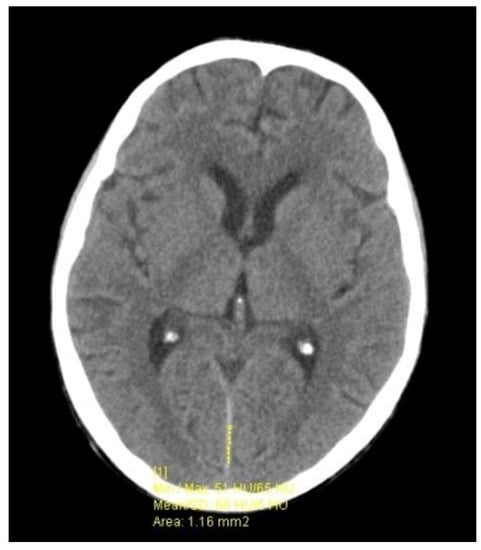

2. Case Presentation